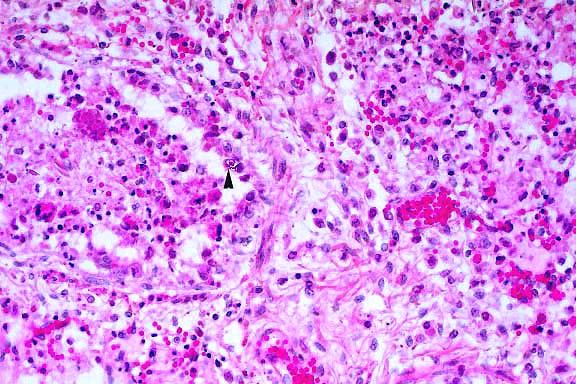

4x

obj

- Case 18-4. The left photo illustrates degeneration

and loss of germ cells with marked dilation of a tubule by dense

aggregates of spermatozoa and secretions (spermatocele). Other

tubules are filled with ill defined debris including multinucleate

giant cells which are barely visible. The image on the right

demonstrates vasculitis and perivasculitis with fibrinoid change.

- AFIP Diagnoses:

- 1. Testis: Degeneration and necrosis, germ cells, with numerous

multinucleate spermatitic giant cells, and multifocal spermatoceles,

Crl:CD (SD) BR rat, rodent.

2. Testis: Vasculitis, chronic-active, focal, moderate, with

fibrinoid change and mild multifocal pericapsular lymphoplasmacytic

perivasculitis and interstitial edema.

3. Epididymis: Sperm granuloma, focal.

Some sections contain peri-epididymal edema.

- Contributor's Diagnoses and Comments:

- 1. Testis: Moderate to severe, segmental testicular degeneration

with giant cell formation, tubular dilation, sperm stasis and

spermatocyte necrosis.

- 2. Moderate to severe, multifocal vasculitis (not all sections).

- 3. Rete testis: Moderate to severe sperm stasis with spermatocele.

- The testicular changes include formation of multinucleated

giant cells (derived from coalescence of spermatids), retention

of spermatozoa with sperm stasis, loss of germ cells (spermatogonia

and spermatocytes) and tubular dilation. Sperm stasis in the

rete testis with spermatocele formation likely contributed to

the tubular dilation. Tubular dilation has also been proposed

to be caused by theophylline suppression of seminiferous tubular

contraction.

- In some sections, there is a vasculitis/perivasculitis of

a testicular blood vessel. Theo-phylline has been reported to

cause vasculitis in rats, primarily affecting the mesenteric

vessels. However, vascular inflammation can be found in many

organs of theophylline-exposed rats.